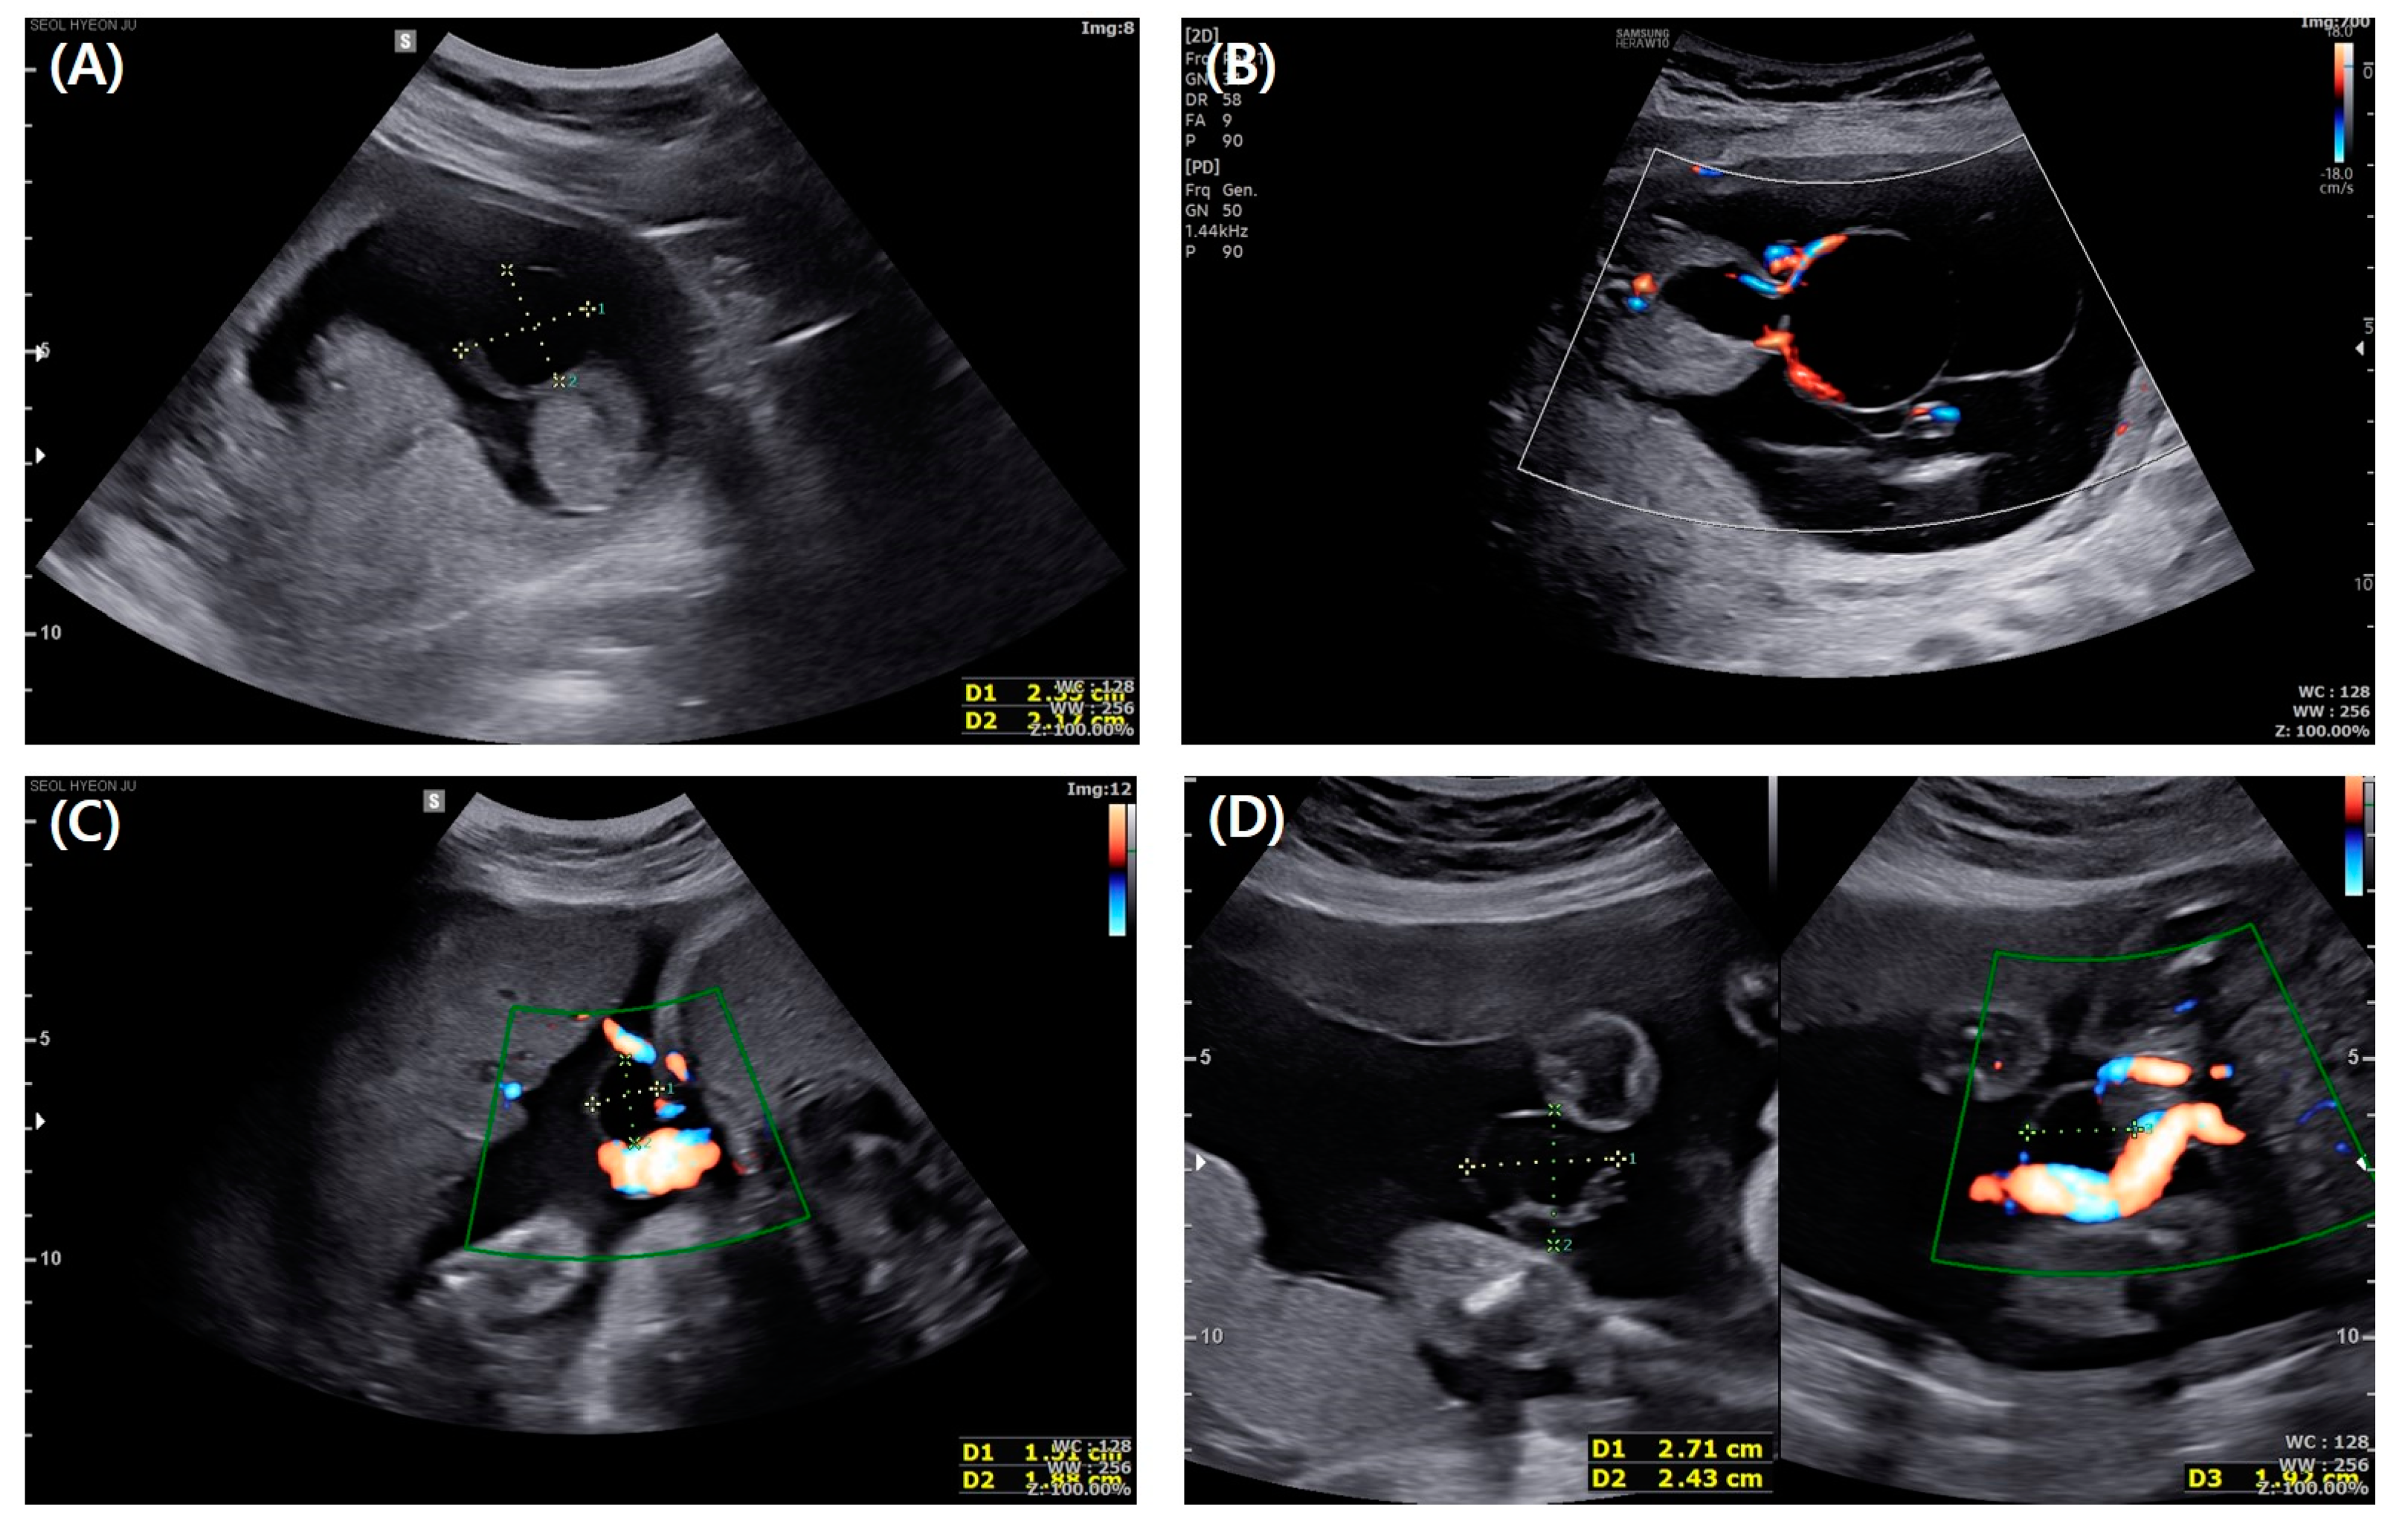

2. Case Presentation